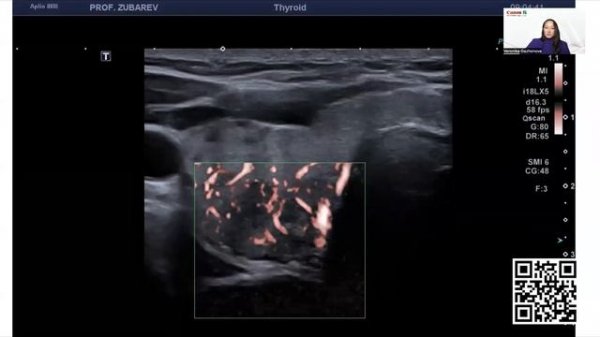

ACR TI-RADS Webinar Part II: Case Based Review & Frequently Asked Questions

Как на практике применять систему отчетности TI-RADS врачу УЗД?

TI-RADS Thyroid Imaging Reporting and Data System Webinar Part III

Система TI-RADS в оценке степени злокачественности узлов щитовидной железы